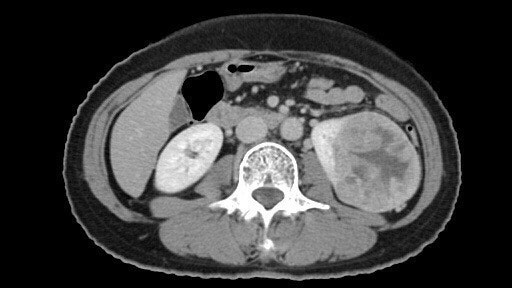

신낭종은 신장에 체액이 고여 생기는 낭종을 말하며 선천성/후천성/단순신낭종/낭성신낭종으로 나눌 수 있습니다. 신장 낭종(신장 낭종)은 신장 낭종(신장 낭종)의 수, 신장 실질이 파괴된 정도, 낭종에 다른 장기가 동반되는지 여부에 따라 분류 및 치료할 수 있습니다. 신장 낭종(신장 낭종)은 대부분의 낭종과 마찬가지로 임상적으로 거의 의미가 없는 단순한 낭종이며 그 원인은 잘 알려져 있지 않습니다. 일종의 노화 현상인 것 같아요. 드물게 신장 낭종(신장 낭종)은 크기가 매우 크거나 합병증이 있는 경우 문제가 될 수 있습니다.신장 낭종 증상

단순 신장 낭종(신장 낭종)은 일반적으로 무증상이지만 신장 낭종(신장 낭종)이 크기가 커지고 다른 장기를 누르면 통증이 발생할 수 있습니다. 드물게 신장 낭종(신장 낭종)의 감염은 발열, 통증 또는 압통을 유발할 수 있으며 신장 낭종(신장 낭종)이 확대로 인해 파열되는 경우 소변 내 혈액이 발생할 수 있습니다. 일반적으로 단순 낭종은 신장 기능 저하를 유발하지 않지만 다낭성 신장 질환은 서서히 신부전으로 진행될 수 있습니다.복부초음파

신장질환 진단에 있어 복부초음파는 가장 흔하고 비침습적이며 많은 정보를 얻을 수 있고 복막 내 다양한 장기를 관찰할 수 있다. 최근에는 건강검진 시 복부 초음파 검사를 자주 시행하여 새로운 종양을 조기에 발견하는 경우가 많습니다. 복부초음파에서 신장에 낭종이 발견되면 단순낭종인지 복합낭종인지 고형종양인지 구분할 수 있다고 합니다. 조영제를 사용한 CT 스캔이 권장됩니다.신장 낭종 치료